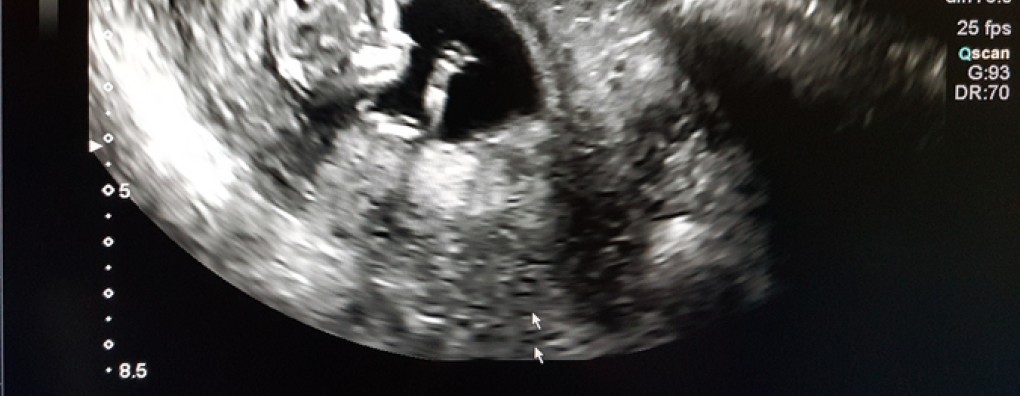

En in het laatste gesprek dat ik met haar voer, daar op die afdeling, merk ik hoe belangrijk het is als zorgverleners in die laatste fase net even buiten de gebaande paden bewegen. “Ik heb mijn kleindochter gezien”, zegt ze. Haar stem breekt, maar het is niet van verdriet. “Op de echo. Ze zwaaide. Tenminste, zo leek het. En nu weet ik… Nu weet ik dat ze er is.”

Wow, het hospice personeel had een echo laborant naar het hospice gehaald en daar een ‘pretecho’ gemaakt. Een wonderbaarlijk simpel cadeau van grote schoonheid.